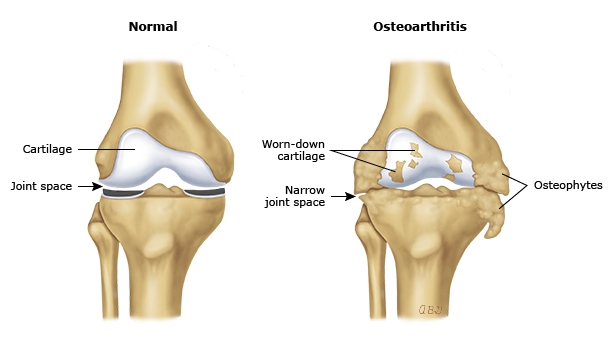

What Is Knee Degeneration?

Knee degeneration, often linked to osteoarthritis (OA), is the gradual breakdown of cartilage in the knee joint. As the cushioning wears away, bones begin to rub against each other—causing pain, stiffness, and reduced mobility.

If untreated, knee degeneration can lead to chronic pain, loss of mobility, and even joint deformity.